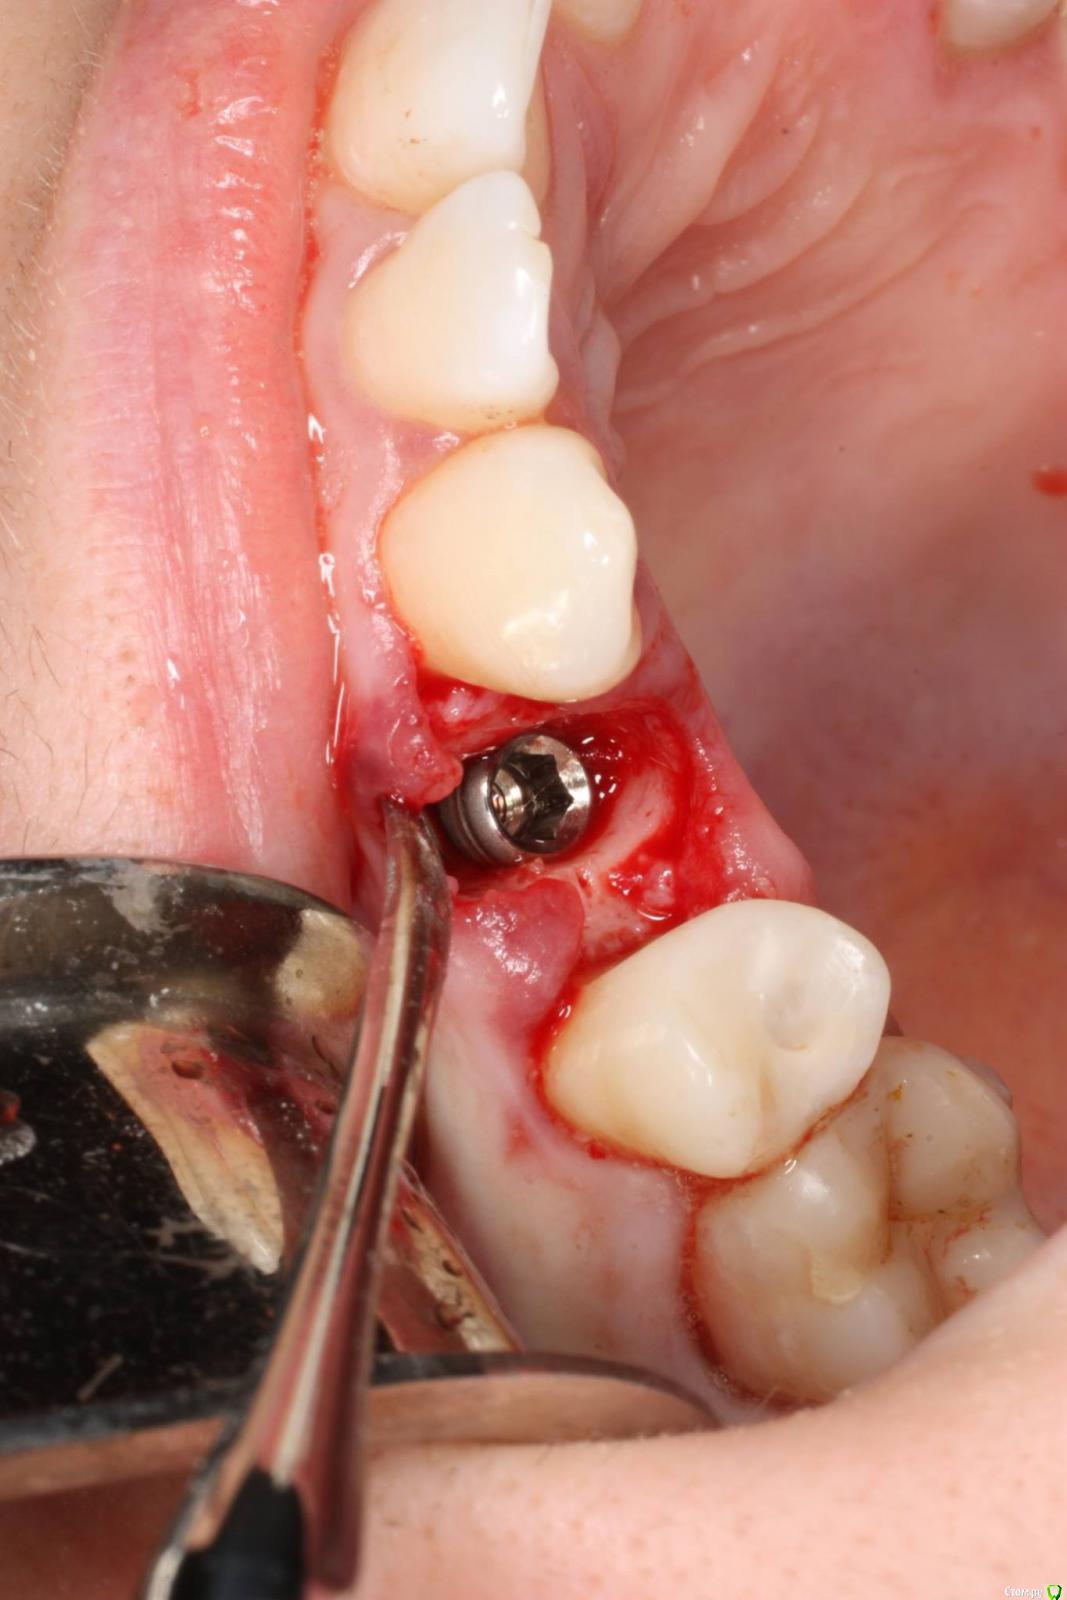

togrul Опубликовано 24 ноября, 2016 Поделиться Опубликовано 24 ноября, 2016 Имплантация проводилась 6 месяцев назад . Пациентка запротезирована. Это моя 2 имплантация была . 7 Ссылка на комментарий

togrul Опубликовано 24 ноября, 2016 Автор Поделиться Опубликовано 24 ноября, 2016 Нет Bio oss использовали . Ссылка на комментарий

syrovovec Опубликовано 24 ноября, 2016 Поделиться Опубликовано 24 ноября, 2016 Графт может и не особо нужен, а сст просится Ссылка на комментарий

АнтонТЛТ Опубликовано 24 ноября, 2016 Поделиться Опубликовано 24 ноября, 2016 Не вижу показаний для сст, коронкой на раз всё отожмётся 2 Ссылка на комментарий